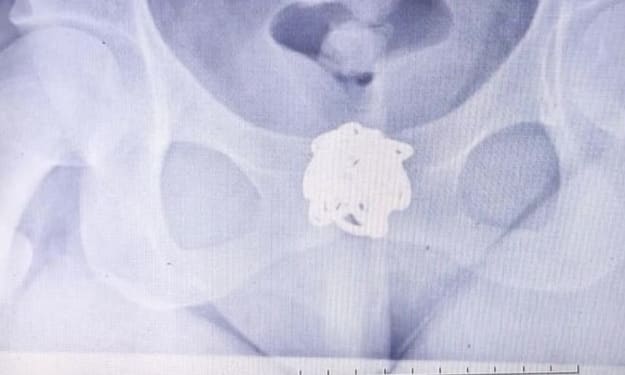

In 2011, something peculiar caught Steve’s attention: a news report about a missing child being rediscovered via age-progression images. Encouraged by the coincidence, Steve visited MissingKids.com and typed terms like “Hawaii,” “male,” “missing 34 years.” There, staring back at him, was an age-progressed photo of a baby who looked strikingly like himself.